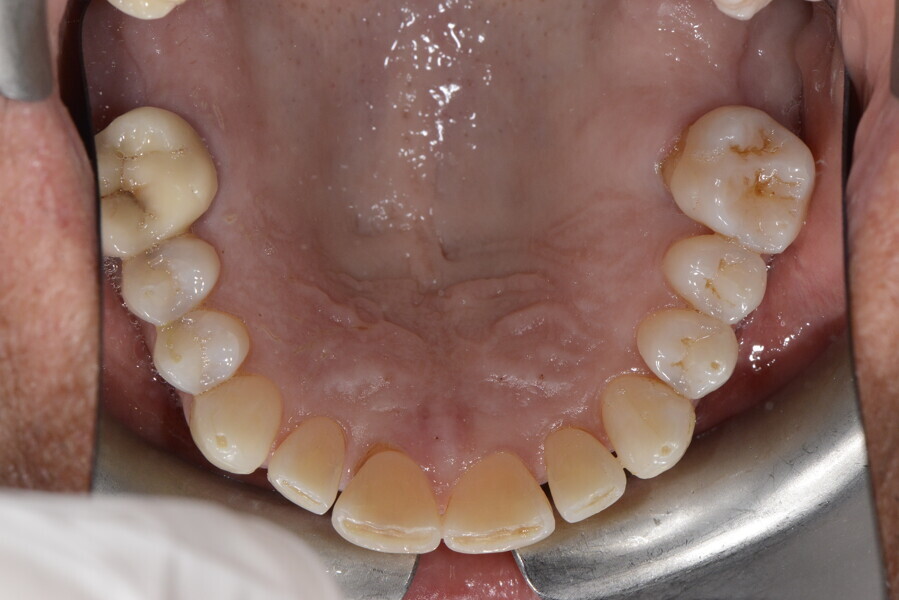

The 58-year-old patient wished to improve his oral aesthetics and function, complaining of mobility of the posterior teeth and wear of the anterior teeth. After data collection, a very complex situation was identified (Figs. 11–13):

1. severe periodontitis with poor prognosis of some teeth;

2. anterior crossbite;

3. severe wear mainly of the anterior teeth and compensatory eruption;38

4. atypical swallowing and lower posture of the tongue at rest;

5. masticatory dysfunction during the mastication test; and

6. no significant signs of temporomandibular disorder.